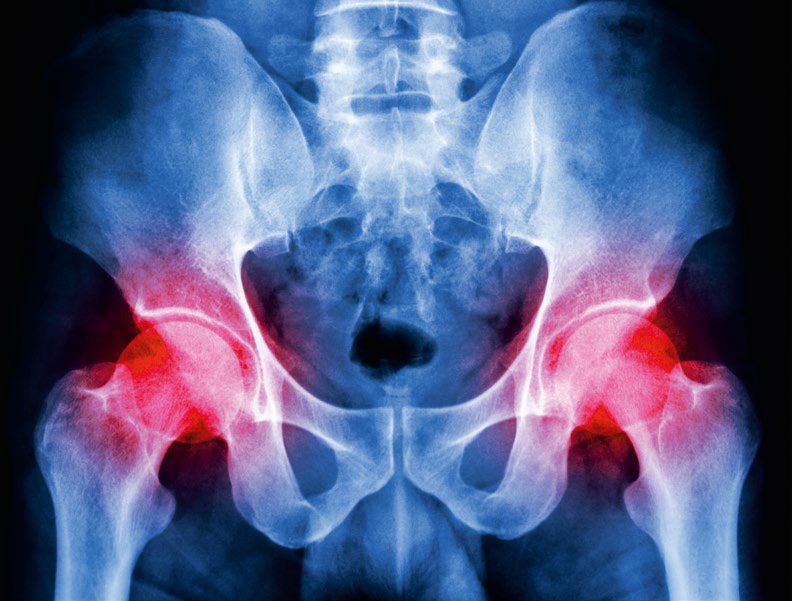

Stawy biodrowe

Koksartroza – objawy

Torebka stawowa wypełniona jest płynem, zwanym mazią, produkowanym przez błonę maziową, w którym zawieszone są komórki tłuszczu i mucyna – składnik, znajdujący się również np. w ślinie, który nadaje lepkość i ma zdolność tworzenia żeli. Ta lepka i płynna zawartość wypełnia przestrzenie między kośćmi, dzięki czemu są blisko siebie, ale tarcie jednej o drugą jest zniwelowane. Wszystko jest dobrze – i nie czujesz, że w ogóle masz te stawy! – jeśli chrząstki w panewce i na głowie kości ślizgają się jedna o drugą, mazi jest wystarczająco dużo, a grubość wspomnianych chrząstek jest odpowiednia. Problem zaczyna się, gdy chrząstka po latach wiernej służby zaczyna się zużywać, a na kościach pojawiają się, bardzo powoli, bo proces ten trwa latami – kostne wyrostki, zwane osteofitami. U różnych osób dochodzi do tego w różnych momentach. Jeśli w czasie, gdy byłeś niemowlakiem stwierdzono u Ciebie dysplazję panewki biodrowej (m.in. dlatego dzieci wkrótce po urodzeniu są badane pod tym kątem przez ortopedów), przeszedłeś ciężkie złamanie w obrębie biodra i głowy kości udowej albo chorujesz na takie choroby, jak reumatoidalne zapalenie stawów czy hemofilię – może to być tzw. wtórna choroba zwyrodnieniowa stawu biodrowego. Jednak większość przypadków tego schorzenia to odmiana pierwotna, która związana jest z wiekiem i starzeniem się organizmu. Chrząstki w całym ciele zużywają się, przez co tracą swoje funkcje amortyzujące, mazistego płynu jest mniej albo zmienia swoją konsystencję i dochodzi do wrażenia, że kość trze o kość. Efektem jest ból, który potęguje to, że na biodrach, jak na solidnym, ale elastycznym stropie, utrzymuje się ciężar ciała.

Zmiany degeneracyjne w obrębie biodra zaczynają się na długo przed tym, jak zaczynasz odczuwać jakikolwiek dyskomfort, nie mówiąc o bólu. Uważa się, że ten proces rozpoczyna się już ok. 35. r. ż. Zaczyna się, jak większość chorób, dość niewinnie, dlatego często przegapiamy pierwsze oznaki i nie podejmujemy środków zaradczych. Możesz odczuwać pewien rodzaj sztywności w biodrach, zwłaszcza gdy długo nie zmieniasz pozycji albo jesteś długo na nogach i nie ruszasz się nadmiernie. Czujesz, że zakres poruszania nogami jest inny i się zmniejsza, a przy jakimś gwałtowniejszym ruchu czujesz ból. Niekiedy wręcz słyszysz swój staw, gdy podczas ruchu trzeszczy i strzyka. O ile nie utrudnia Ci to codziennego funkcjonowania, często pewnie machasz na to ręką. Aż przychodzi moment, że zaczyna boleć tak, że utrudnione jest chodzenie, siadanie i wstawanie, np. ciężko Ci wysiąść z samochodu lub podnieść się z głębokiego fotela. Widzisz objawy koksartrozy – tak brzmi inne medyczne określenie tego schorzenia.